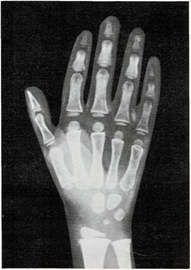

Mi madre me respondió: “Una razón de que lo encuentres blando es que sus huesos no son tan duros como los tuyos. Los niños, al nacer, tienen muy pocos huesos duros. Los huesos de su esqueleto se componen sobre todo de cartílago. Pero las células óseas trabajan sin descanso, y por ello sus huesos crecen y se endurecen muy deprisa. Tus huesos son más largos y duros que los del niño. Los huesos seguirán creciendo y se endurecerán hasta tus veinte años.

Una vez el médico me hizo una radiografía de la muñeca. Quería ver cómo crecían mis huesos. Yo le pregunté cómo era posible que mediante una foto de mis huesos pudiera saber qué le pasaba a mi esqueleto.

El médico me respondió: “Tu muñeca tiene ocho huesos. Pero no todos crecen a la vez. Los huesos de la muñeca de algunos niños crecen más deprisa o más despacio que los de otros niños. Pero los huesos de la muñeca crecen a un mismo ritmo en todos los niños sanos. Si los huesos de tu muñeca salen bien en la radiografía, quiere decir que el resto de los huesos de tu cuerpo también están bien.”

En ella ya se ven claramente los ocho huesos.